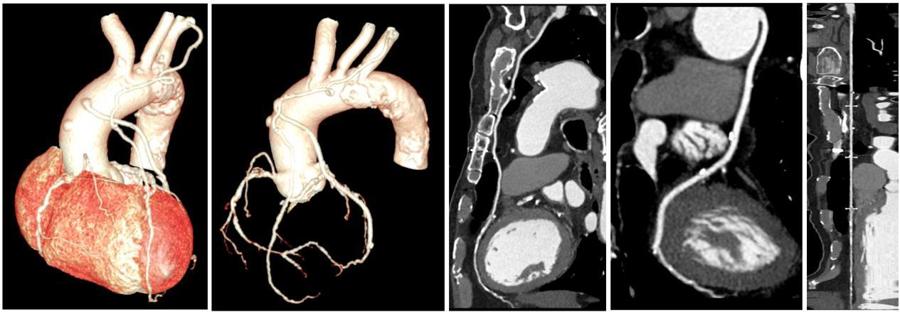

更全面:一站式全身扫描

该CT拥有16厘米宽体等焦宝石DOD探测器,是目前业内最宽探测器,百万像素超高分辨率检查+3mm超低密度分辨率,将小病灶显示得更清楚、边界更清晰。可轻松覆盖心脏、颅脑、肝脏等器官,搭配独有的自由组合一站式联合扫描技术,能够一次性实现多血管或多器官联合扫描,大幅提升胸痛三联征、冠脉多部位联合扫描、心脑血管上下肢及胸腹血管病变的检出率,为让患者得到及时科学有效的诊疗提供了强有力的技术保障。

对比传统CT检查一个部位需要注射一次造影剂,Revolution CT可以注射一次造影剂,一次性完成冠状动脉CTA、肺动脉CTA及主动脉CTA等多部位CTA检查,得到高对比度的影像图,不仅安全,还省心省力省时更省钱。